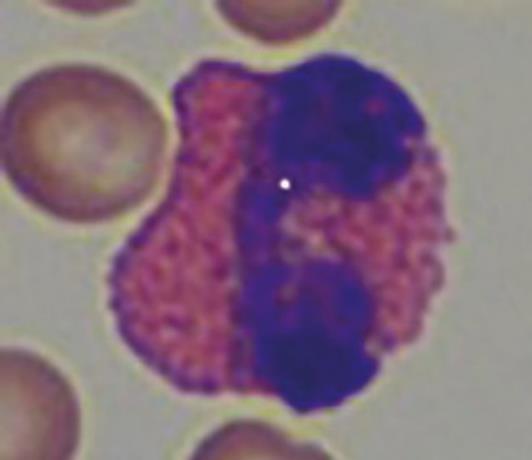

Eosinophilia occurs, in contrast to rabbits, not only by tissue injury and infections of tissue containing mastocytes (skin, lungs, gastrointestinal tract, uterus), but also by parasitosis.

- Fig. 5: Eosinophil granulocyte